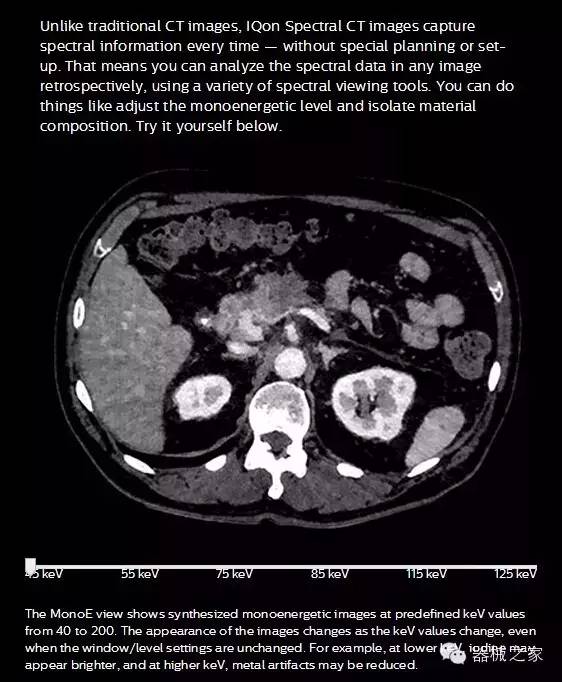

IQon光譜CT能夠按照需求提供光譜量化和工具,并能通過簡單工作流程、在低劑量下對結(jié)構(gòu)進行定性分析

IQon光譜CT -- 是業(yè)界首臺以探測器為成像基礎的光譜CT,它可以在單次常規(guī)掃描下獲得傳統(tǒng)解剖影像及光譜功能影像。不僅可以提供精準的診斷信息,還可簡化工作流程、在低劑量下完成定量與定性分析。